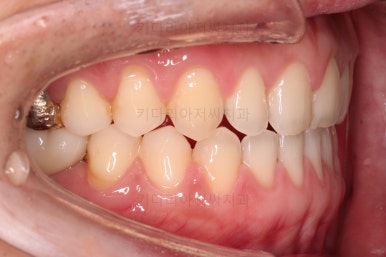

교정치료도 종료 되었고 연산동임플란트 잘 완성이 되었어요.

총 14개월이 걸린 치료였는데 비교적 짧은 기간 내에 틈새도 모으고, 임플란트 및 충치치료도 다 완료를 할 수 있었습니다.

전후 사진을 비교해 볼게요.

비교적 짧은 시간 안에 환자분이 만족하는 치료를 할 수 있었어요.